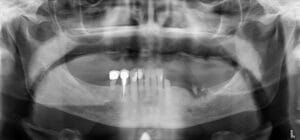

We use a CBCT (cone beam CT) scan alongside digital impressions and photography to create a precise 3D model of your mouth. This allows us to plan your implant placement virtually.

Using a 3D navigation system, our dentists position implants digitally at the perfect angle and depth. This plan is then transferred into a customised surgical guide and if needed temporary teeth, which can be placed directly onto the newly placed implants.

A dental navigation system is a computer-aided tool that guides dentists during implant placement. It merges CBCT scans with digital impressions to create a virtual 3D model of your mouth. The system then provides real-time guidance so the implant is positioned at the exact angle, depth, and location planned in advance. This improves accuracy, reduces invasiveness, and ensures long-lasting results compared with freehand placement.